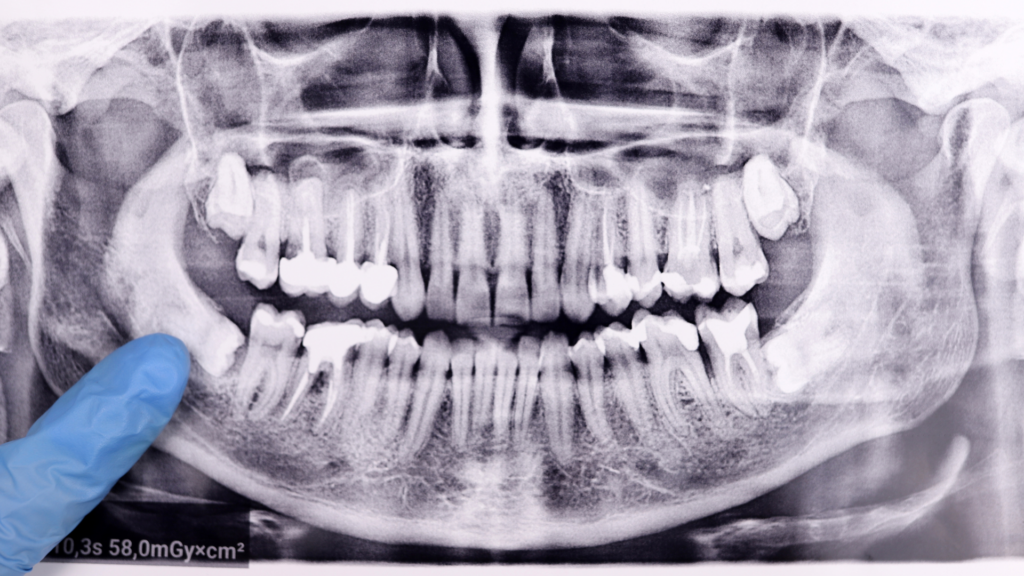

Repair Your Smile With Full Mouth Reconstruction in Los Angeles: Here’s What to Know